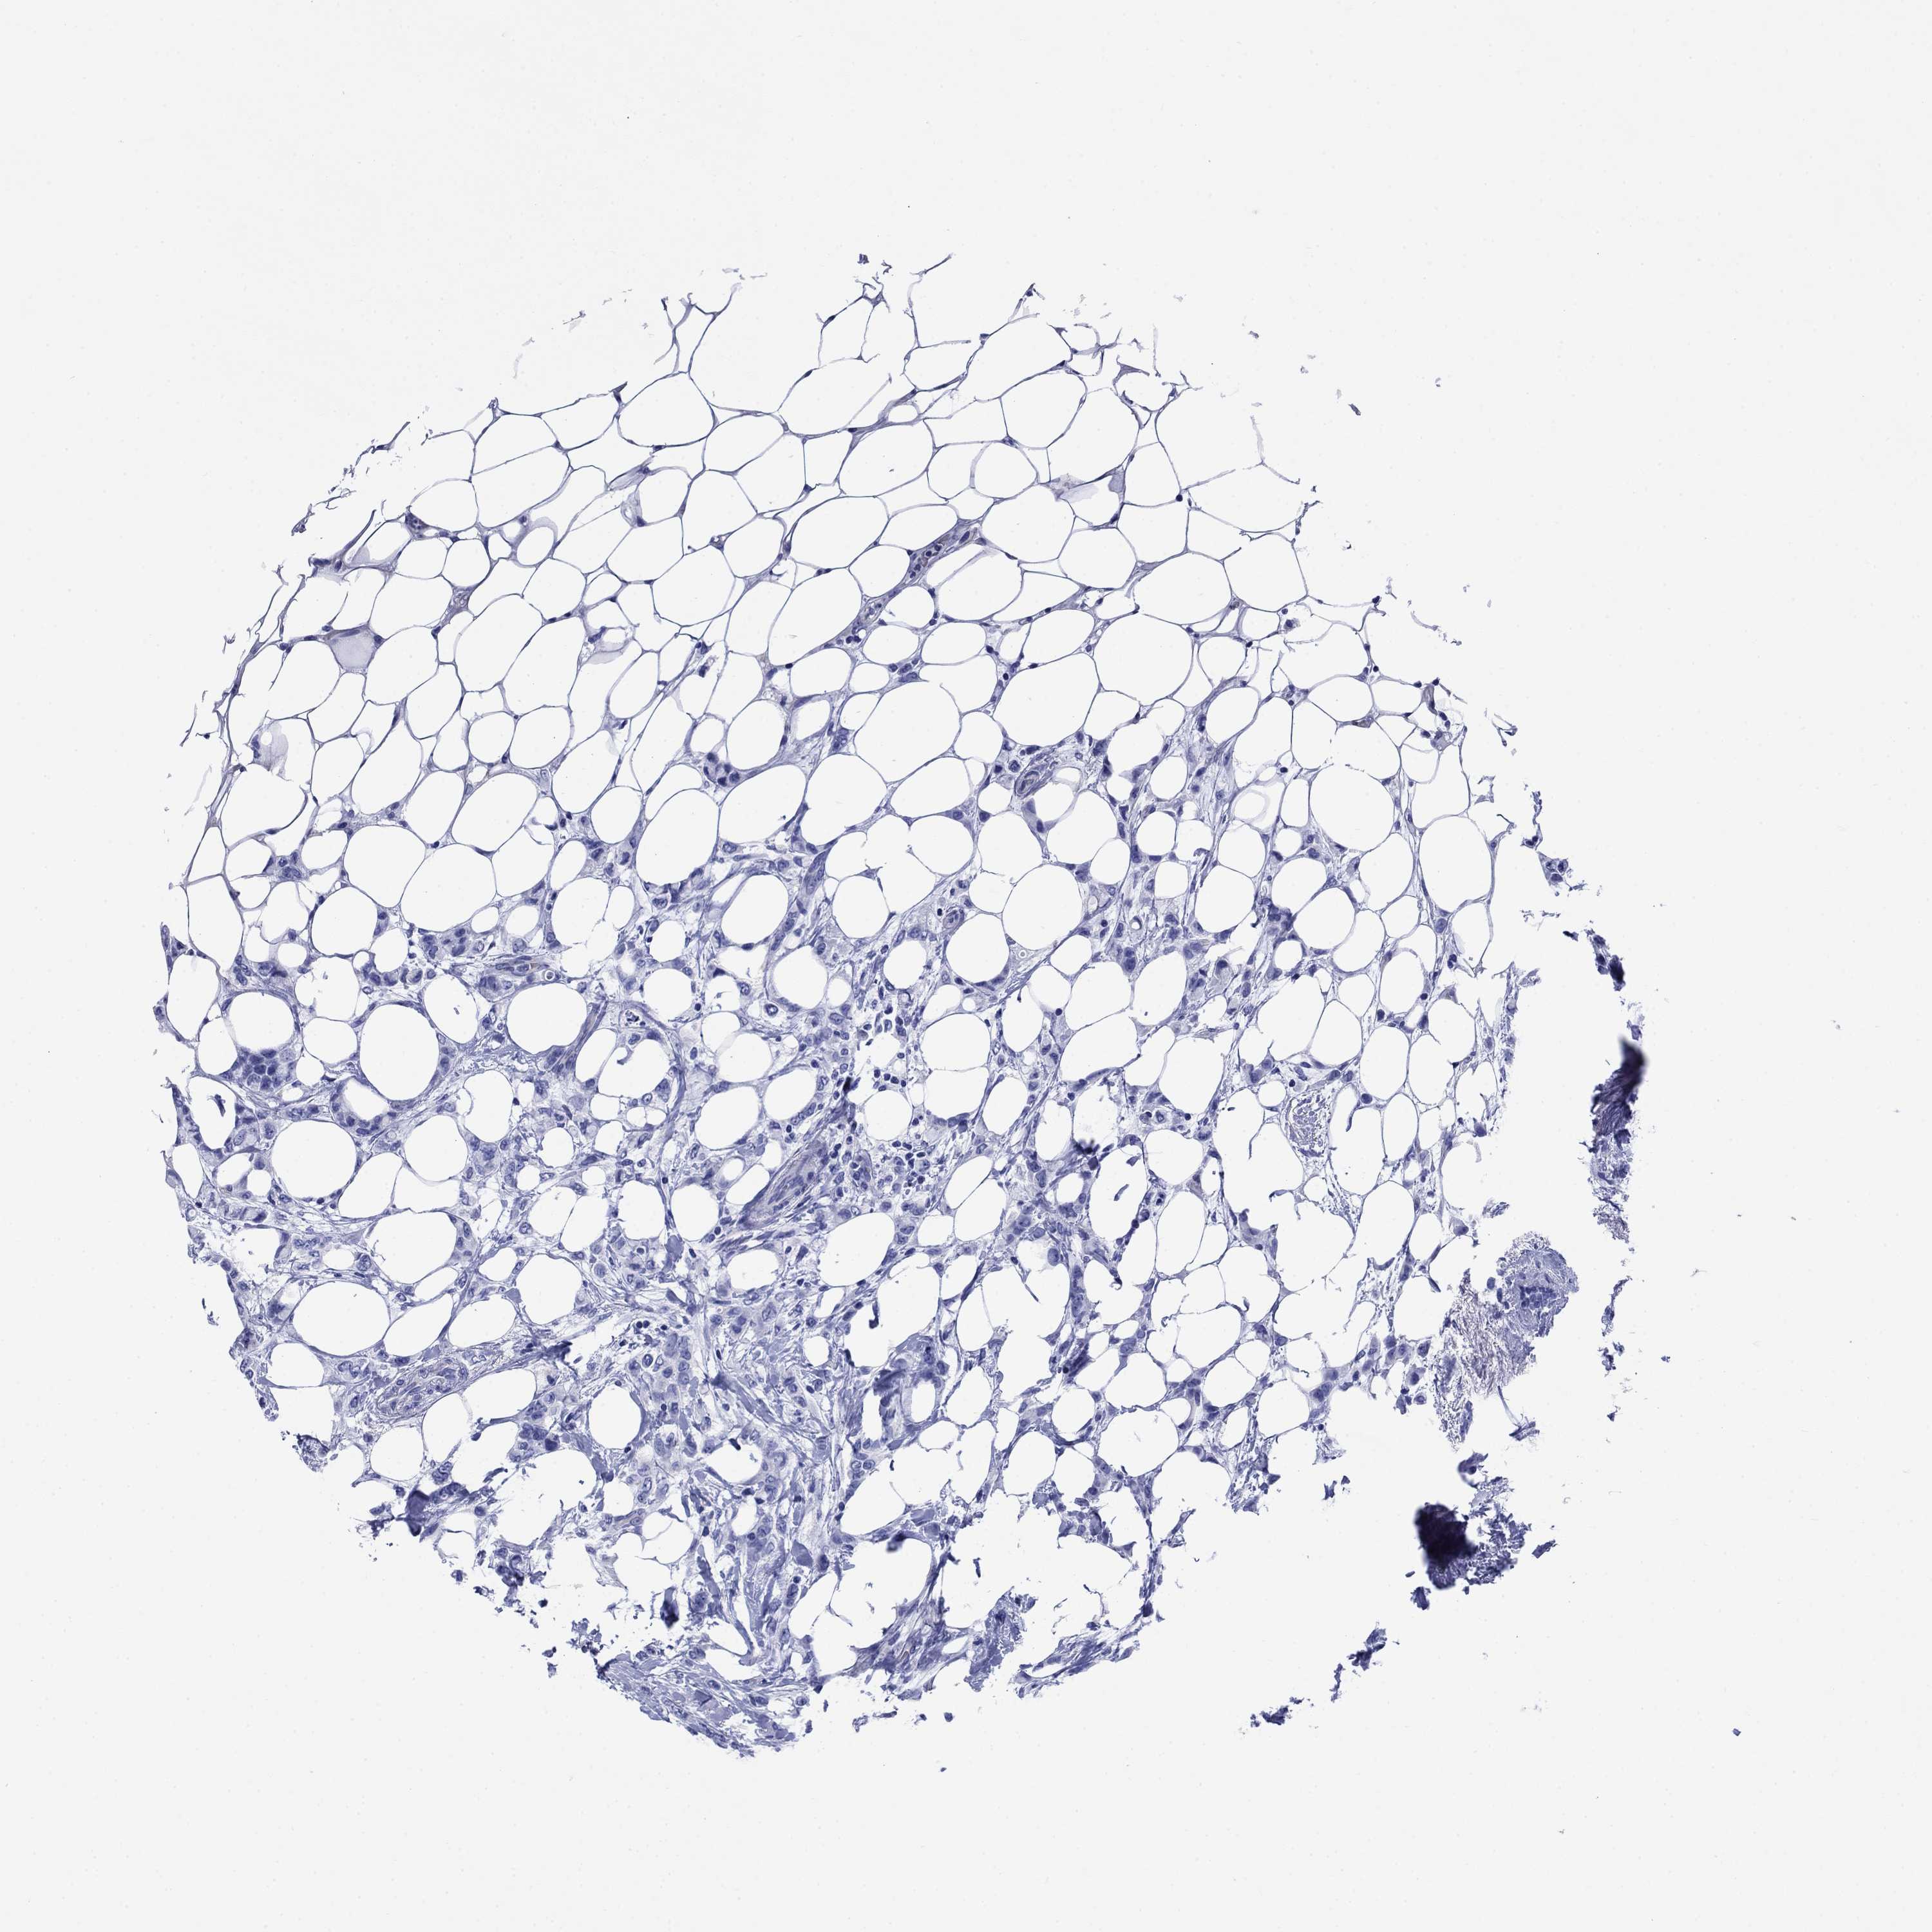

CANCER BREAST CANCER Show tissue menu

Breast cancer

Human cancer